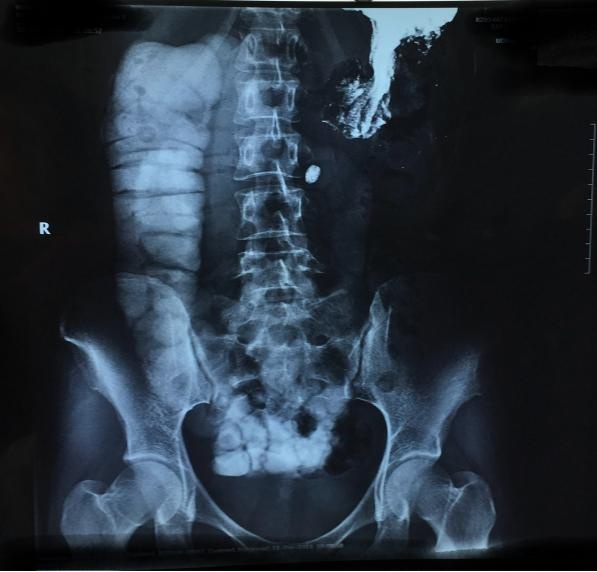

患者手术前反复发作肠梗阻的影像资料